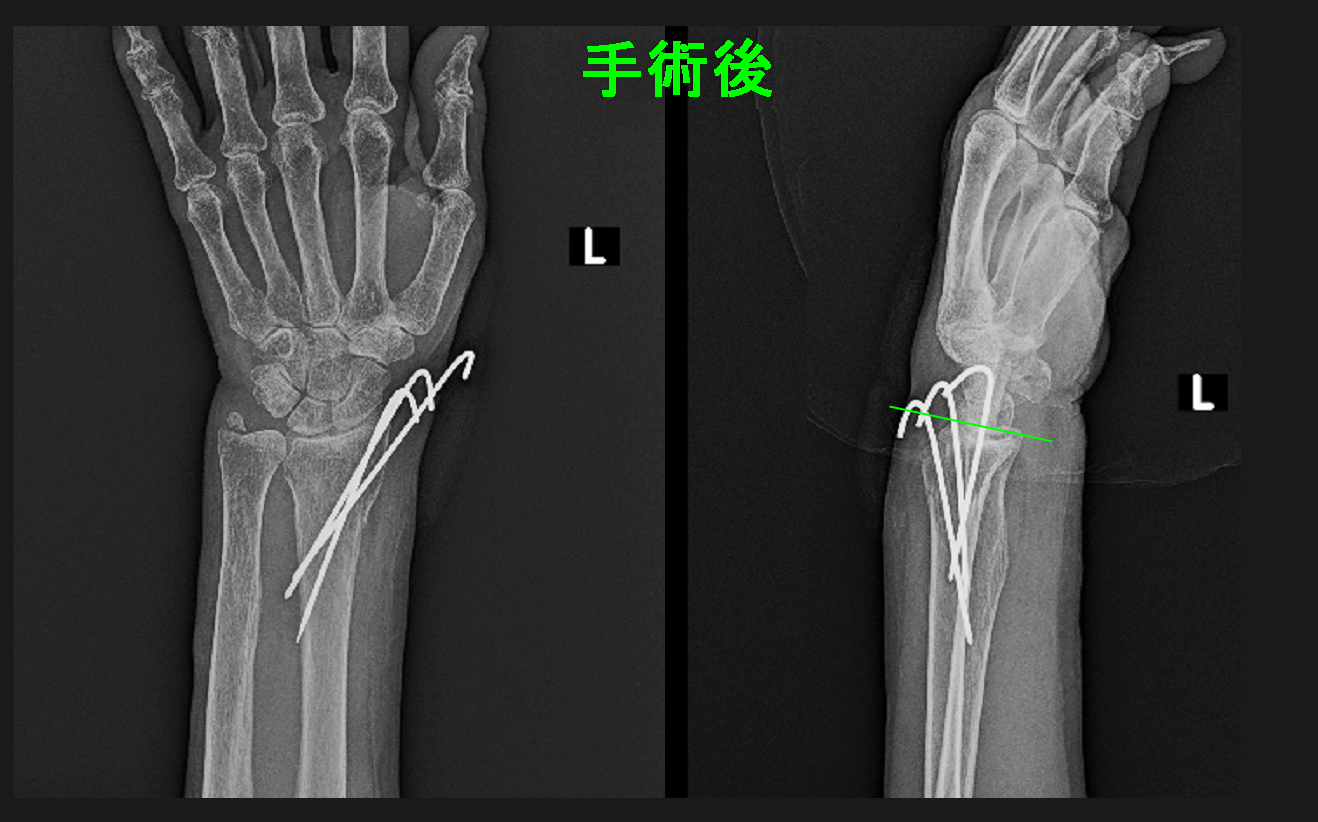

そのため、当院では整復した骨折を鋼線という針金3本で固定して、さらにギプス固定を行うようにしています。針金もギプスも5週間で除去しています。

術後Xp.jpg

手術後、手関節の傾斜は手のひら側に傾いています。患者さんは(麻酔の注射が多少痛かったけれど)手術は痛くなかったと言っていました。